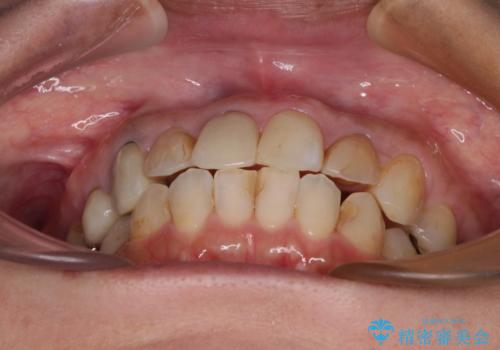

- 上下前歯のデコボコを気にして来院された患者様です。

歯列としては、ワイヤー装置でもインビザラインでも、どちらでも対応可能でしたが、処置されている歯が多く、ワイヤー装置を装着するためには処置歯のやり直しが必要な状態でした。

インビザラインでもアタッチメントを装着できないという同様のデメリットがありますが、比較的矯正治療を行いやすい歯列であったので、インビザラインによる矯正治療を行うこととしました。